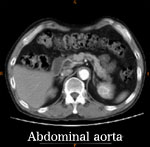

症例5

74歳 男性

【主 訴】

検診異常, 間歇性跛行

【起始・経過】

かねてより、100mの間歇性跛行。

平成11年、腹部大動脈瘤を指摘された。

平成18年1月CTにて増大傾向を認め当院紹介受診。

AAA size 5.2 cm

【既往歴】

74歳 HCC→TAE

高血圧(+) 糖尿病(−) 喫煙歴(−)

【治療計画】

AAA stent graft(Cook Zenith) + Lt iliac stenting + Lt internal iliac embolization

Pre-operative CAT scan